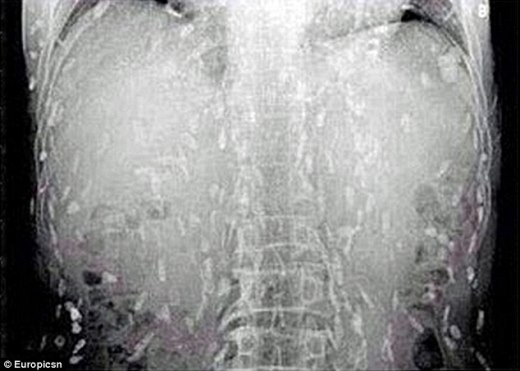

Sashimi (cá sống cắt lát) được xem là một món cực ngon và đắt trong thực đơn sushi, thế nhưng một người đàn ông đã bị chính món ăn hấp dẫn này làm nguy hiểm đến tính mạng vì gây nhiễm sán dây.

Một người đàn ông Trung Quốc đã phải tìm đến bác sĩ vì bị đau dạ dày và ngứa ngáy da nhiều ngày liền. Sau khi được chụp x-quang, người đàn ông đã “tá hỏa” vì toàn bộ cơ thể đã bị lây nhiễm sán dây do ăn quá nhiều sashimi.